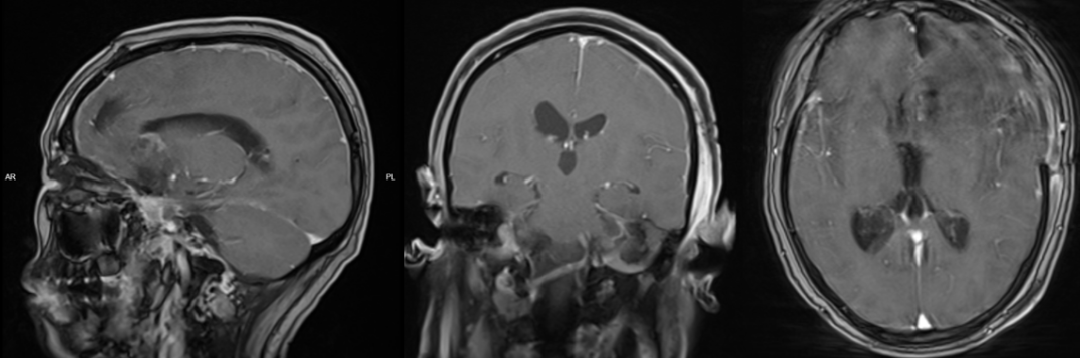

患者女性,38岁,头痛一年余,加重2月入院。

入院查体:患者意识清楚,对答切题,双侧瞳孔等大等圆,双侧瞳孔等大等圆,对光反射正常,四肢活动好,肌力及肌张力正常。头颅磁共振提示左侧额顶部占位,考虑胶质母细胞瘤。

术前磁共振:

术后磁共振:

图39. 术后患者意识清楚,肢体及言语功能活动好,暂出院以待进一步放化疗治疗